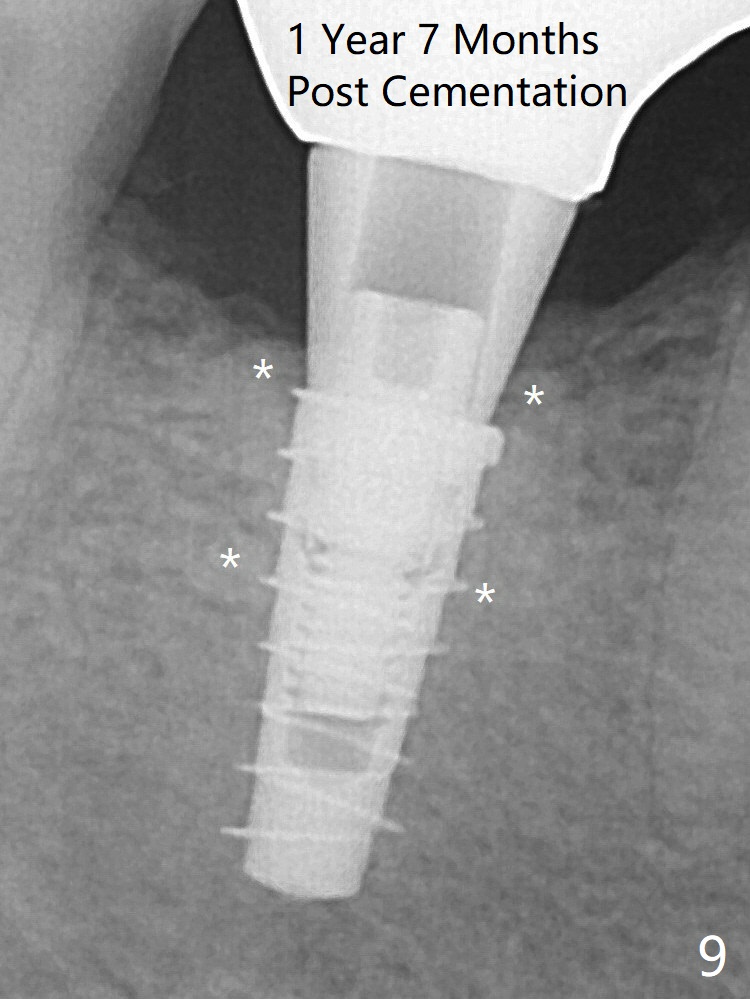

For safety, a 4x9 mm IBS implant is placed with insertion torque 40 Ncm; a 5x5.7(4) mm abutment is immediately placed for an immediate provisional to cover the large socket and keep Vera graft in place (Fig.4 *). Yellow dashed line: apical osteotomy; red dashed line: Mental Loop. Impression is taken nearly 3 months postop (Fig.6). The bone density around the implant increases 7 months post cementation (Fig.8 *). The higher density bone seems to extend coronally 1 year 7 months post cementation (Fig.9). The dense bone apparently extends toward the abutment as well 3 years 5 months post cementation (Fig.10 curved arrows).